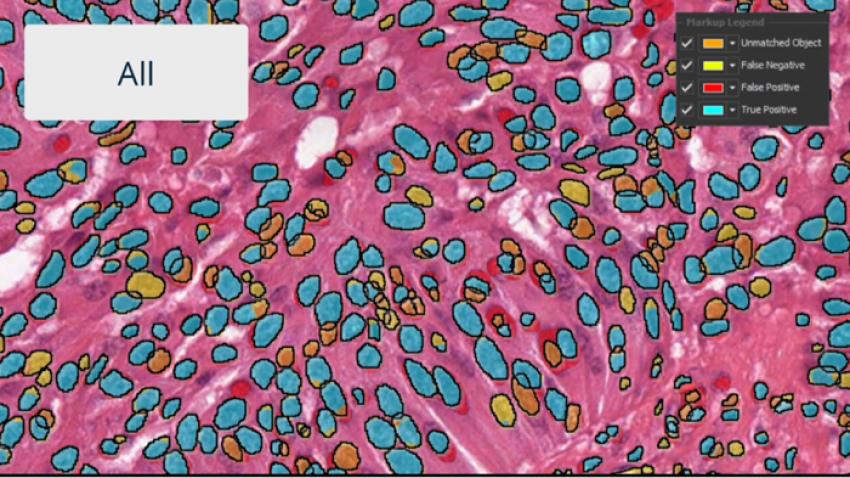

Investigate results with interactive markup images where you can toggle on and off each population of interest. Interactive markups can be combined with probability thresholding and are especially valuable in exploring validation outputs.

Use real-time tuning in HALO AI to watch a network as it trains in real time. Toggle the mark up on and off to evaluate performance, choose to add training data, or change parameters on-the-fly.